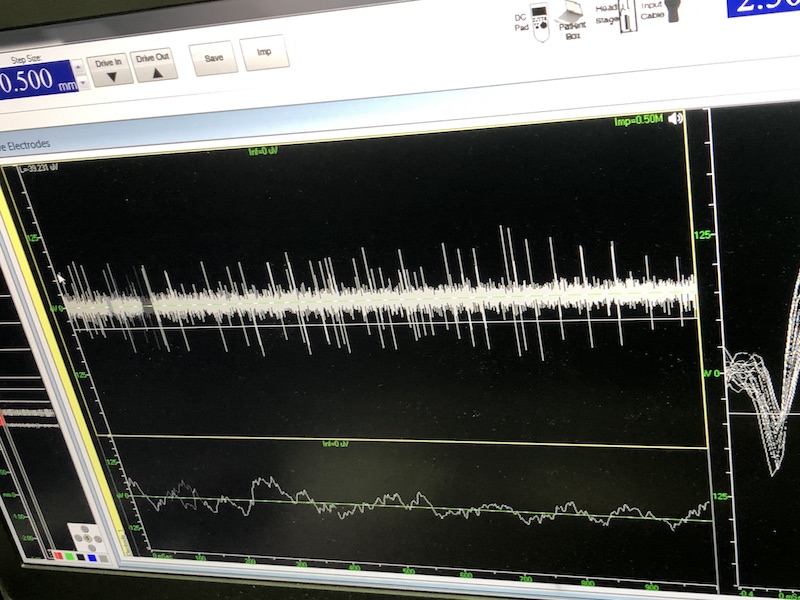

與此同時,檢測電極實時記錄電極末端每一點處的電信號,當(dāng)電極逐漸接近手術(shù)規(guī)劃靶點時,借助電信號的特征,醫(yī)生可以判斷電極是否已經(jīng)沿長軸植入患者顱內(nèi)的目標(biāo)核團,以及植入的準(zhǔn)確長度。下圖中,檢測信號屬于典型的核團信號,證明電極已經(jīng)抵達(dá)相對理想的植入位置,記錄下此刻的位置后,即可在相應(yīng)位置植入刺激電極。

檢測核團信號